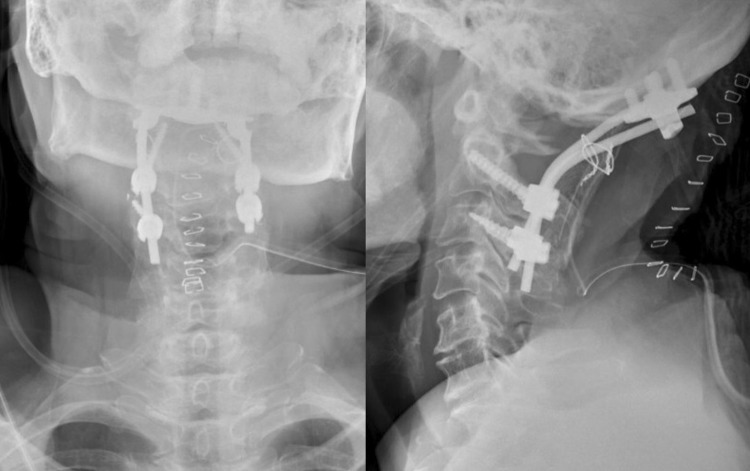

Fig. 9.

Postoperative plain radiographs of the cervical spine in anteroposterior and lateral views showed occipito-C3 fusion using occipital plate, C2 pedicle screws, and C3 lateral mass screws with iliac strut bone graft